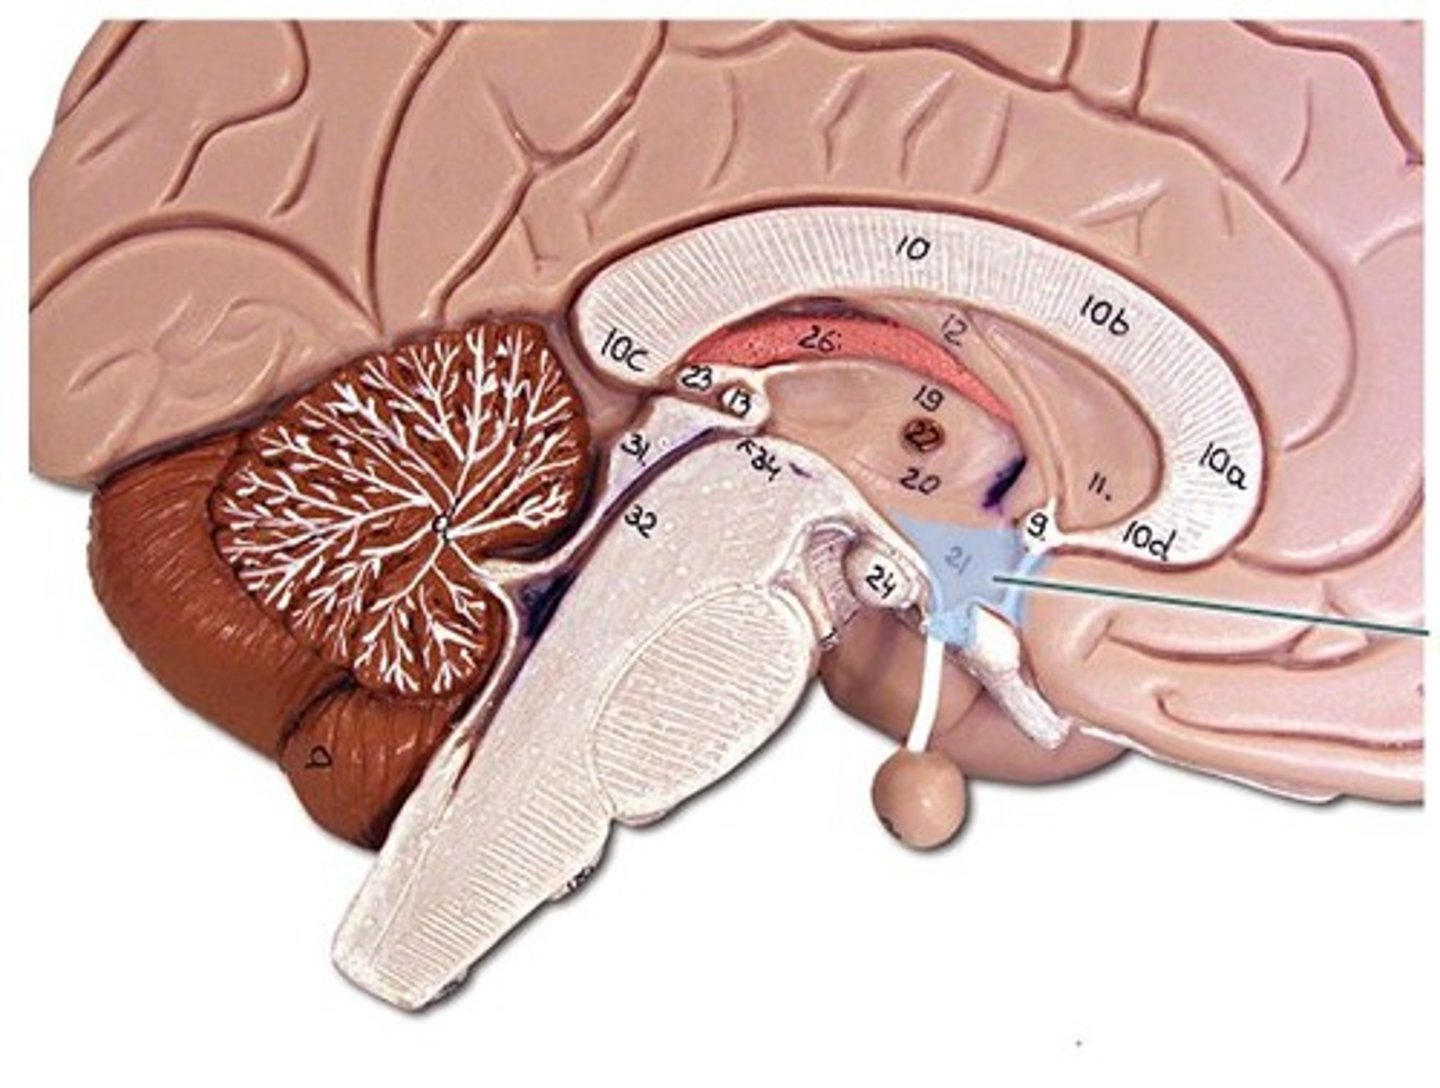

corpus callosum

septum pellucidum

fornix

internal capsule

right and left lateral ventricles

third ventricle

fourth ventricle

cerebral aqueduct (mesencephalic aqueduct)

interventricular foramen

thalamus

hypothalamus

cerebellum

arbor vitae

tentorium cerebelli

between cerebrum and cerebellum